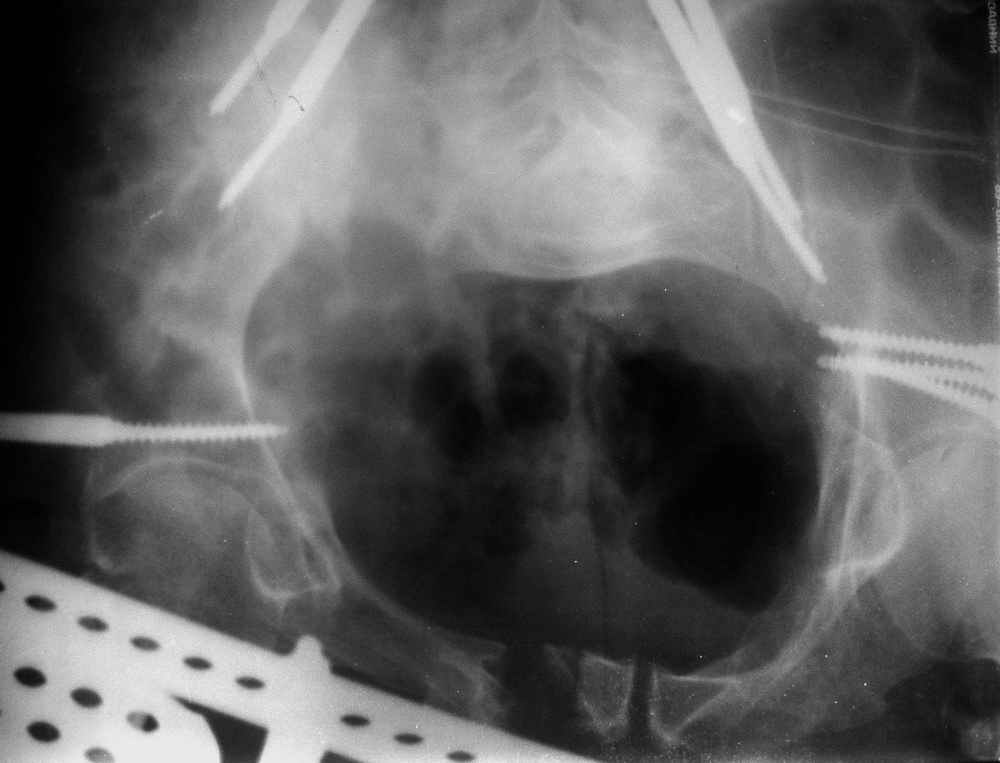

Пример лечения стабильной деформации с вертикальным смещением половины таза.

отеотомия передних и задних отделов, дистракция аппаратом

окончательная фиксация